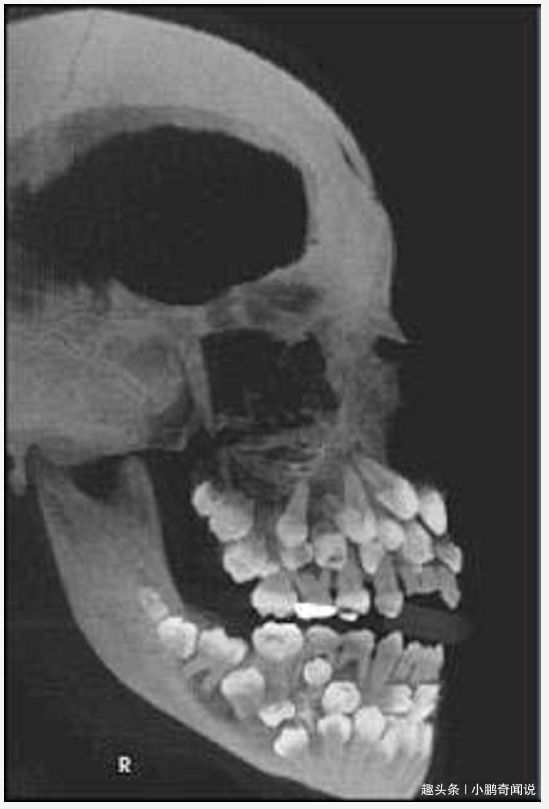

8岁男孩嘴里长上百颗牙齿,x光拍出来的照片不忍直视!